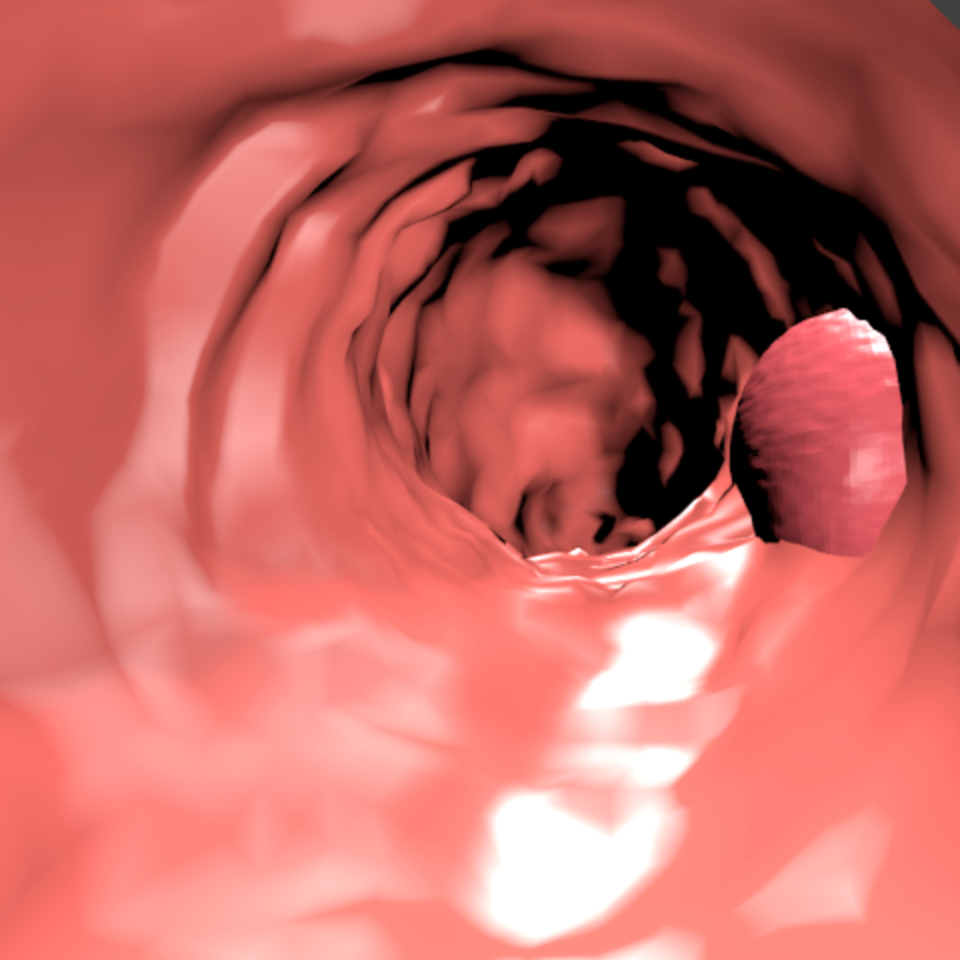

Our 3D colons structure is a cone composed by 2454 faces. Vertices are randomly displaced following a normal distribution in order to simulate the tissues in the colon. Additionally, the colon structure is modified by displacing 7 segments as in Figure 3. For the textures we used a base color [0.80, 0.13, 0.18] (RGB). For each sample we shift the color to other tones of brown, orange and pink. One single polyp is used on every image, which is placed inside the colon. It can be either in the colon’s walls or in the middle. Polyps are distorted spheres with 16384 faces. Samples with polyps occupying less than 20,000 pixels are removed.

Lighting is composed by a white ambient light, two white dynamic lights that project glare into the walls, and three negative lights that project black light at the end of the colon. We found that having a dark area at the end helps CycleGAN to understand the structure of the colon. The 3D scene must be similar to real colon images because otherwise, the CycleGAN will not translate properly the images to the real-world domain. Figure 4 illustrates the images and ground truth generated by the 3D engine.

4 Synth-Colon

We publicly release Synth-Colon, a synthetic dataset for polyp segmentation. It is the first dataset generated using zero annotations from medical professionals. The dataset is composed of 20 000 images with a resolution of 500500. Synth-Colon additionally includes realistic colon images generated with our CycleGAN and the Kvasir training set images. Synth-Colon can also be used for the colon depth estimation task [12] because we provide depth and 3D information for each image. Figure 1 shows some examples from the dataset. In summary, Synth-Colon includes: